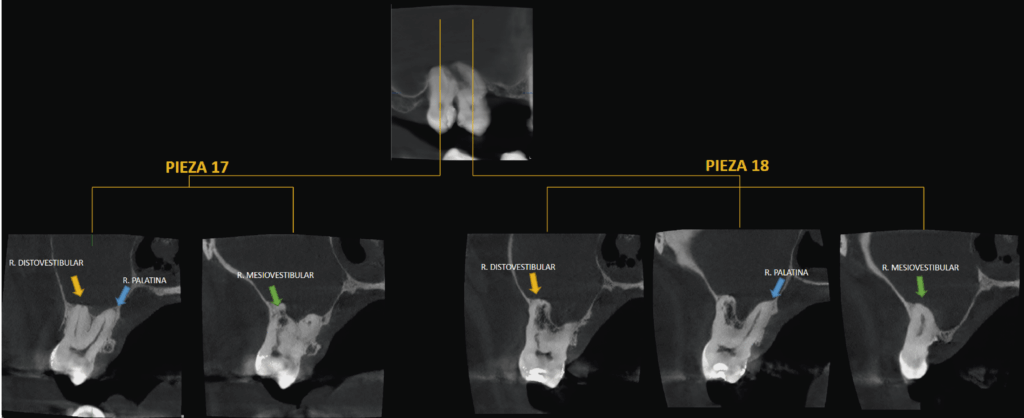

A la evaluación de la tomografía de campo reducido con un tamaño de voxel de 0.75 mm se pudo observar el seno maxilar derecho con presencia de contenido isodenso compatible con sinusitis de origen no odontogénico. Asimismo, se evidencio una reabsorción radicular externa por aposición que compromete la raíz mesiovestibular de la pieza 18 y la raíz distovestibular de la pieza 17 y que se extendía hasta conducto pulpar (visto en cortes tangenciales y axiales) y finalmente se observó hipercementosis de ambas piezas y ausencia del espacio para el ligamento periodontal perirradicular a predominio de zona interproximal de las raíces palatinas compatible con concrescencia.

CORTES TANGENCIALES